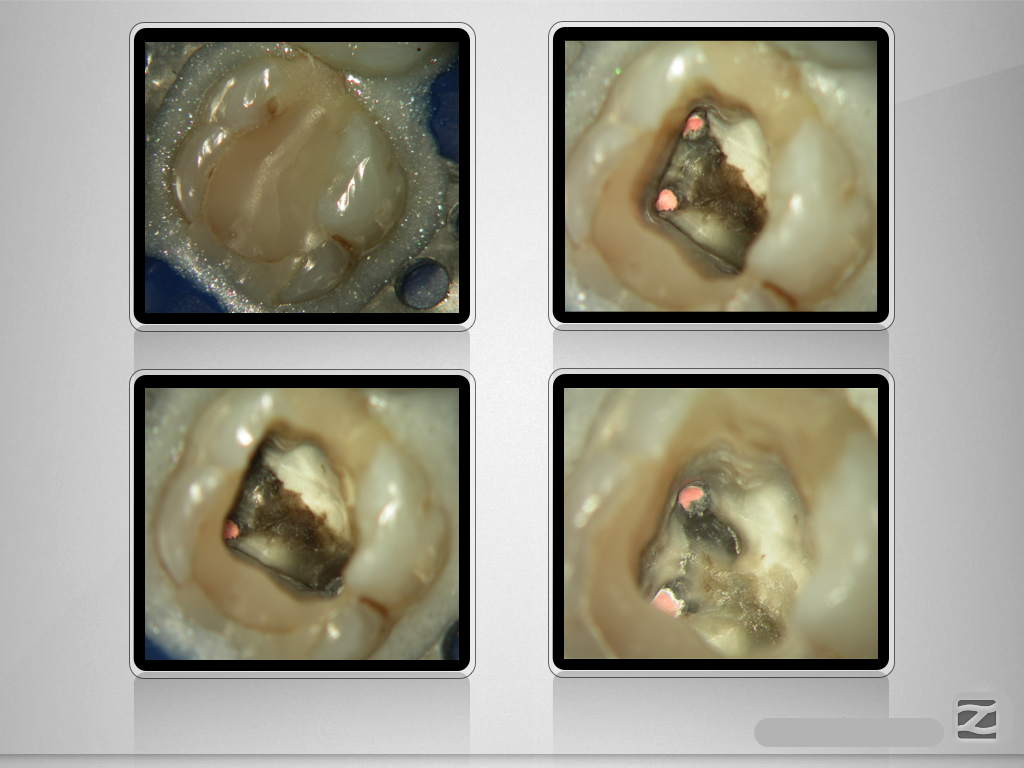

26D.002

Entwarnung